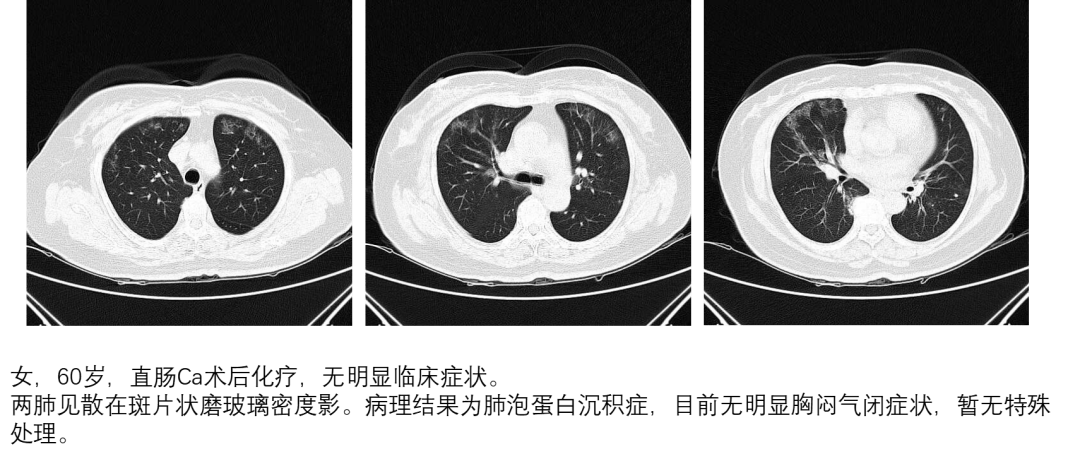

肺蛋白沉积症是一种罕见的疾病,它会导致异常蛋白质在肺部沉积,影响呼吸功能。作为一名医生,我亲眼目睹了许多患者因此疾病而受到困扰。在这篇文章中,我将探讨肺蛋白沉积症带来的挑战以及我们应对这些挑战的方法。

肺蛋白沉积症的早期症状往往不明显,容易被忽视。然而,及早发现并进行诊断和治疗是至关重要的。我们需要通过临床检查、影像学和组织活检等手段来确定诊断,并针对患者制定个体化的治疗方案。药物治疗、支持性护理和康复训练都是有效的治疗手段。